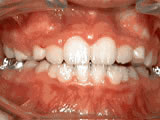

Teeth Crowding

Treated with braces for 26 months, starting at age 11 — now enjoying a confident new smile.

Teeth Crowding before Teeth Crowding after